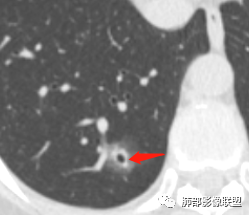

晨读:52f,体检发现右下肺结节,空洞、周围晕征(磨玻璃),局部血管影增粗,考虑1.真菌感染;2.GPA或不典型单发转移待排。

晨读:体检发现肺部结节,胸部CT:右下肺混合密度结节,结节中心空泡,壁光滑,结节边缘模糊,软毛刺,结节血管相对清楚,考虑良性结节可能,抗炎后复查。

右下肺混合磨玻璃结节,其内见空洞,空洞壁光滑,结节周围可见晕征,可见增粗血管,首次体检发现患者无症状,还是建议抗炎2周,1个月后复查,鉴别腺癌。

右肺下叶混合磨玻璃结节,边缘清晰,有分叶,毛刺,内见空泡。考虑腺癌。常规可以抗炎后复查。

体检发现肺部结节,右下肺混合密度结节,结节中心空泡,壁光滑,结节边缘模糊,血管在结节内增粗,矢状位前基底段还有一片磨玻璃影,所以考虑良性结节可能,炎性肉芽肿?抗炎后复查。腺癌合并炎性改变待排。

晨读病例,右肺下叶小结节病灶,内可见光滑空洞,周围可见边缘模糊磨玻璃影,首先考虑感染性病变,真菌或结核可能,鉴别腺癌,后者小病灶空洞少见,周围磨玻璃影清晰,胸膜凹陷征。

病灶大部分磨玻璃边界是模糊的,但有些地方还是比较清楚,腺癌是不能完全排除的,建议1个月后复查。

mGGO,周围有晕,边界不清,空洞,收缩力不强,血管通过走形正常,首先考虑炎性结节,抗炎和复查。筛查真菌。

内部低密度是空洞还是扩张的细支气管有疑问,边缘有的层面清楚有的层面模糊,恶性待排吧。

右肺下叶混合磨玻璃结节,边缘清晰,有分叶,毛刺,内见空泡。考虑腺癌。

我未见过的类型,CT征像良恶参半。女性,52岁,腺癌的好发人群。良性征像外周纯磨玻璃影很大,而且境界欠清晰。恶性征像,中央薄壁气囊边缘实性增厚,而而且厚薄不均匀。结合性别年龄,腺癌首先考虑,处理:随访3-6月,看看实性部分有无增多,应该不影响生存率。

磨玻璃结节,中央有空洞,周围晕征,磨玻璃血运明显,考虑腺癌,鉴别隐球菌。

晨读:结节伴晕,晕模糊,内有小空洞,周边还有片状模糊影,支持首先考虑炎性,临床会先抗感染治疗后复查。

晨读:右下肺结节,结节中心小空洞,壁光滑,结节周围有晕,边缘模糊,其他基底段亦可见斑片磨玻璃影,考虑炎性肉芽肿。隐球?寄生虫?

晨读:中老年女性,体检来诊。右肺下叶后基底段近胸膜下mGGN,其内实性成分似见毛刺及分叶,并见空泡征,周围GGO边界清楚,近肺门端见血管影伸入病灶并略显扩张,病变与支气管关系观察欠佳。多考虑恶性,腺癌可能性大。鉴于首次检查,常规建议抗炎治疗后复查,观察病灶变化情况,再决定下一步诊疗方向。

晨读,中老年女性,右下肺混合磨玻璃结节,边界模糊,内有空泡,张力高,考虑支气管扩张,周围血管相连,稍有增粗,考虑良性病变,细支气管扩张畸形并周围炎。腺癌待排。

晨读,女,52岁体检发现结节,右肺下叶见磨玻璃样结节影,边缘见毛刺,病灶内可见小空泡影,考虑腺癌可能,待除外炎性病变。

病灶内低密度像扩张的支气管,整体被病灶包围,可以定为空泡,PC没有这么大的牵拉,曲霉的话病变范围太小,而且是体检发现。病灶周围磨玻璃似清非清,病灶下缘磨玻璃是明确清晰的,因此诊断倾向于粘液腺癌,比较心虚的地方是没有抗炎复查。

右肺下叶后基底段混合型磨玻璃结节,边缘见晕征,内见小空泡/空洞,其内壁光整,与支气管关系不密切,常规考虑炎性肉芽肿病变,结核/隐球菌可能,腺癌待排,建议抗炎1月后复查。

右下叶后基底段混合密度结节,边缘磨玻璃模糊,晕征,中心实性成分似有多个小结节融合,收缩力不明显,中心空泡样改变内缘光滑,考虑小空洞,综合考虑良性炎性结节,隐球可能,结核与曲霉待鉴别。抗炎后复查或穿刺活检。

右肺下叶混合磨玻璃结节,中心有小透光区,壁光整,磨玻璃边缘模糊,收缩力不明显,考虑炎性结节,抗炎治疗后复查,代排隐球菌。

右肺下叶基底段胸膜下小结节,周围模糊晕征,其内光滑囊腔影,考虑小空洞,其内血管走形自然,周围软毛刺,常规考虑炎性结节,隐球可能性大,建议抗感染后复查,鉴别粘液腺癌。

从那么多天以来的读片结果看,不要走寻常路,各位老师考虑炎性的多,小隐球结节还是实性的多(见得少不知道对不对),空洞张力较高,那我考虑腺癌。